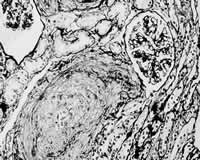

入院当日,患者尿量1750 mk,尿沉渣镜检:红细胞8~10 个/高倍视野,正常形态100 %;24 h尿蛋白定量0.39 g(参考值:<0.15 g)。予甲泼尼龙1 g/d×3日静点,继以泼尼松60 mg/d口服。冲击治疗次日,患者腹痛缓解,但尿量仅300 mk,血钾6.78 mmok/L,遂行血液透析。冲击治疗结束当日,患者无诱因再次出现腹痛,尿色呈洗肉水样,体温最高39.2 ℃。腹痛为上腹部两侧持续性绞窄性剧烈疼痛,无放射,不伴尿急、尿痛、呕吐、腹泻。查体:腹膜刺激征阴性,肠鸣音存在,双肾区叩痛阳性。实验室检查:血小板(PLT)计数下降,(116×109 /L→47×109 /L);激活的部分凝血活酶时间(APTT)58.4 s(参考值:28~42 s);血浆鱼精蛋白副凝试验阴性(参考值:阴性),优球蛋白溶解时间>90 s(参考值:<90 s)。腹部平片和B超未见异常;双肾动、静脉及肠系膜上动脉彩超未见异常。因观察到患者腹痛在血液透析开始后1 h左右明显减轻,而在血液透析结束后数小时又加重,故推测腹痛减轻与血液透析中应用肝素有关,遂于5月1日起予低分子肝素钙(速避凝)0.1 mg/d皮下注射。抗凝治疗2天后,患者腹痛缓解,体温正常,血小板计数、APTT逐渐恢复正常。住院期间,相隔8周两次查狼疮抗凝物(LA)阳性(参考值:阴性),抗心磷脂抗体(ACL)阴性(参考值:阴性)。5月30日,在全麻下行开放性肾活检术,病理结果:光镜下可见肾小动脉多数血栓形成,内膜呈葱皮样增厚,管腔狭窄及闭塞,多数肾小球呈缺血性皱缩,部分呈缺血性硬化;免疫荧光全部阴性(图1,图2)。住院期间,患者肾功能无恢复,予泼尼松60 mg/d 12周后逐渐减量),2001年8月出院。

图1 肾小动脉血栓形成,管腔几乎闭塞;肾小球呈缺血性皱缩改变。(HE染色,×200)

APS可累及多系统,肾脏是APS的主要靶器官之一。APS的肾脏病理改变主要为肾血管血栓形成,从肾血管主干到肾小球毛细血管的各级血管均可受累,以血栓性微血管病(TMA)最为典型。光镜下,TMA在急性期可表现为内皮细胞肿胀、变性,血管壁纤维素样坏死,血管腔内血栓形成;在慢性期则可见血管壁增生性改变,血栓部分再通等。免疫荧光检查应无免疫复合物沉积。APS的肾脏损害在临床上可表现为不同程度的蛋白尿、高血压、肾功能损害,严重者可致急性肾衰,当发生肾梗死时可表现为腰痛、腹痛、肉眼血尿等。APS所致肾脏TMA是本例急性肾衰的原因。